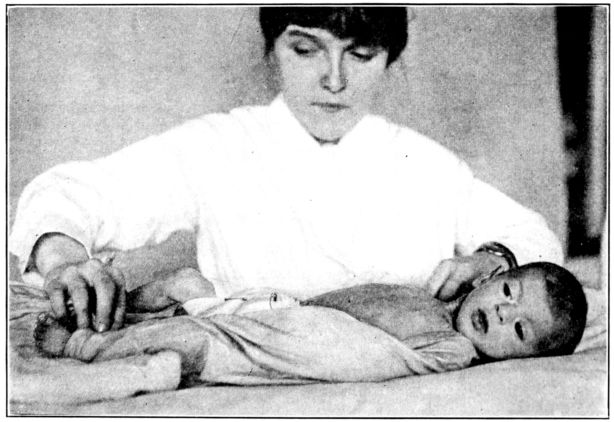

| 180. | Baby wrapped in blanket preparatory to gavage | 523 |

| 181. | Gavage | 524 |